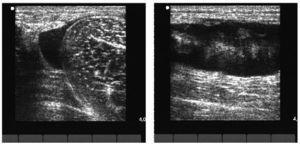

El estudio ecográfico mostró de nuevo colección anecoica de 5 × 10 (fig. 2) y la imagen de RM puso de manifiesto una colección purulenta en el tercio proximal de tensor del músculo de la fascia lata (fig. 3).

Figura 3 Imágenes en STIR en el plano coronal. Se demuestran extensos cambios de señal que afectan al músculo tensor de la fascia lata derecho con presencia de una colección líquida y absceso de 7 cm de diámetro longitudinal por 4 y 2,5 cm en el plano transversal. Se observan importantes cambios edematosos en su masa muscular, así como la presencia de un importante edema en el tejido graso celular subcutáneo con una pequeña colección que desciende por la cara anterolateral del muslo.